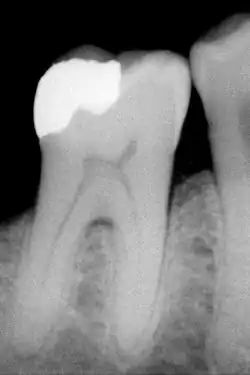

The large amount of mineral in enamel accounts not only for its strength but also for its brittleness.[6] Tooth enamel ranks 5 on Mohs hardness scale (between steel and titanium) and has a Young's modulus of 83 GPa.[4] Dentin, less mineralized and less brittle, 3–4 in hardness, compensates for enamel and is necessary as a support.[7] On radiographs, the differences in the mineralization of different portions of the tooth and surrounding periodontium can be noted; enamel appears lighter than dentin or pulp since it is denser than both and more radiopaque.[8]

The high mineral content of enamel, which makes this tissue the hardest in the human body, also makes it demineralize in a process that often occurs as dental caries, otherwise known as cavities.[15] Demineralization occurs for several reasons, but the most important cause of tooth decay is the ingestion of fermentable carbohydrates. Tooth cavities are caused when acids dissolve tooth enamel:[24] Enamel is also lost through tooth wear and enamel fractures.[25]

Sugars and acids from candies, soft drinks, and fruit juices play a significant role in tooth decay, and consequently in enamel destruction.[26] The mouth contains a great number and variety of bacteria, and when sucrose, the most common of sugars, coats the surface of the mouth, some intraoral bacteria interact with it and form lactic acid, which decreases the pH in the mouth.[27] The critical pH for tooth enamel is generally accepted to be pH 5.5. When acids are present and the critical pH is reached, the hydroxyapatite crystallites of enamel demineralize, allowing for greater bacterial invasion deeper into the tooth. The most important bacterium involved with tooth decay is Streptococcus mutans, but the number and type of bacteria varies with the progress of tooth destruction.[27]

Furthermore, tooth morphology dictates that the most common site for the initiation of dental caries is in the deep grooves, pits, and fissures of enamel. This is expected because these locations are impossible to reach with a toothbrush and allow for bacteria to reside there. When demineralization of enamel occurs, a dentist can use a sharp instrument, such as a dental explorer, and "feel a stick" at the location of the decay. As enamel continues to become less mineralized and is unable to prevent the encroachment of bacteria, the underlying dentin becomes affected as well. When dentin, which normally supports enamel, is destroyed by a physiologic condition or by decay, enamel is unable to compensate for its brittleness and breaks away from the tooth easily.